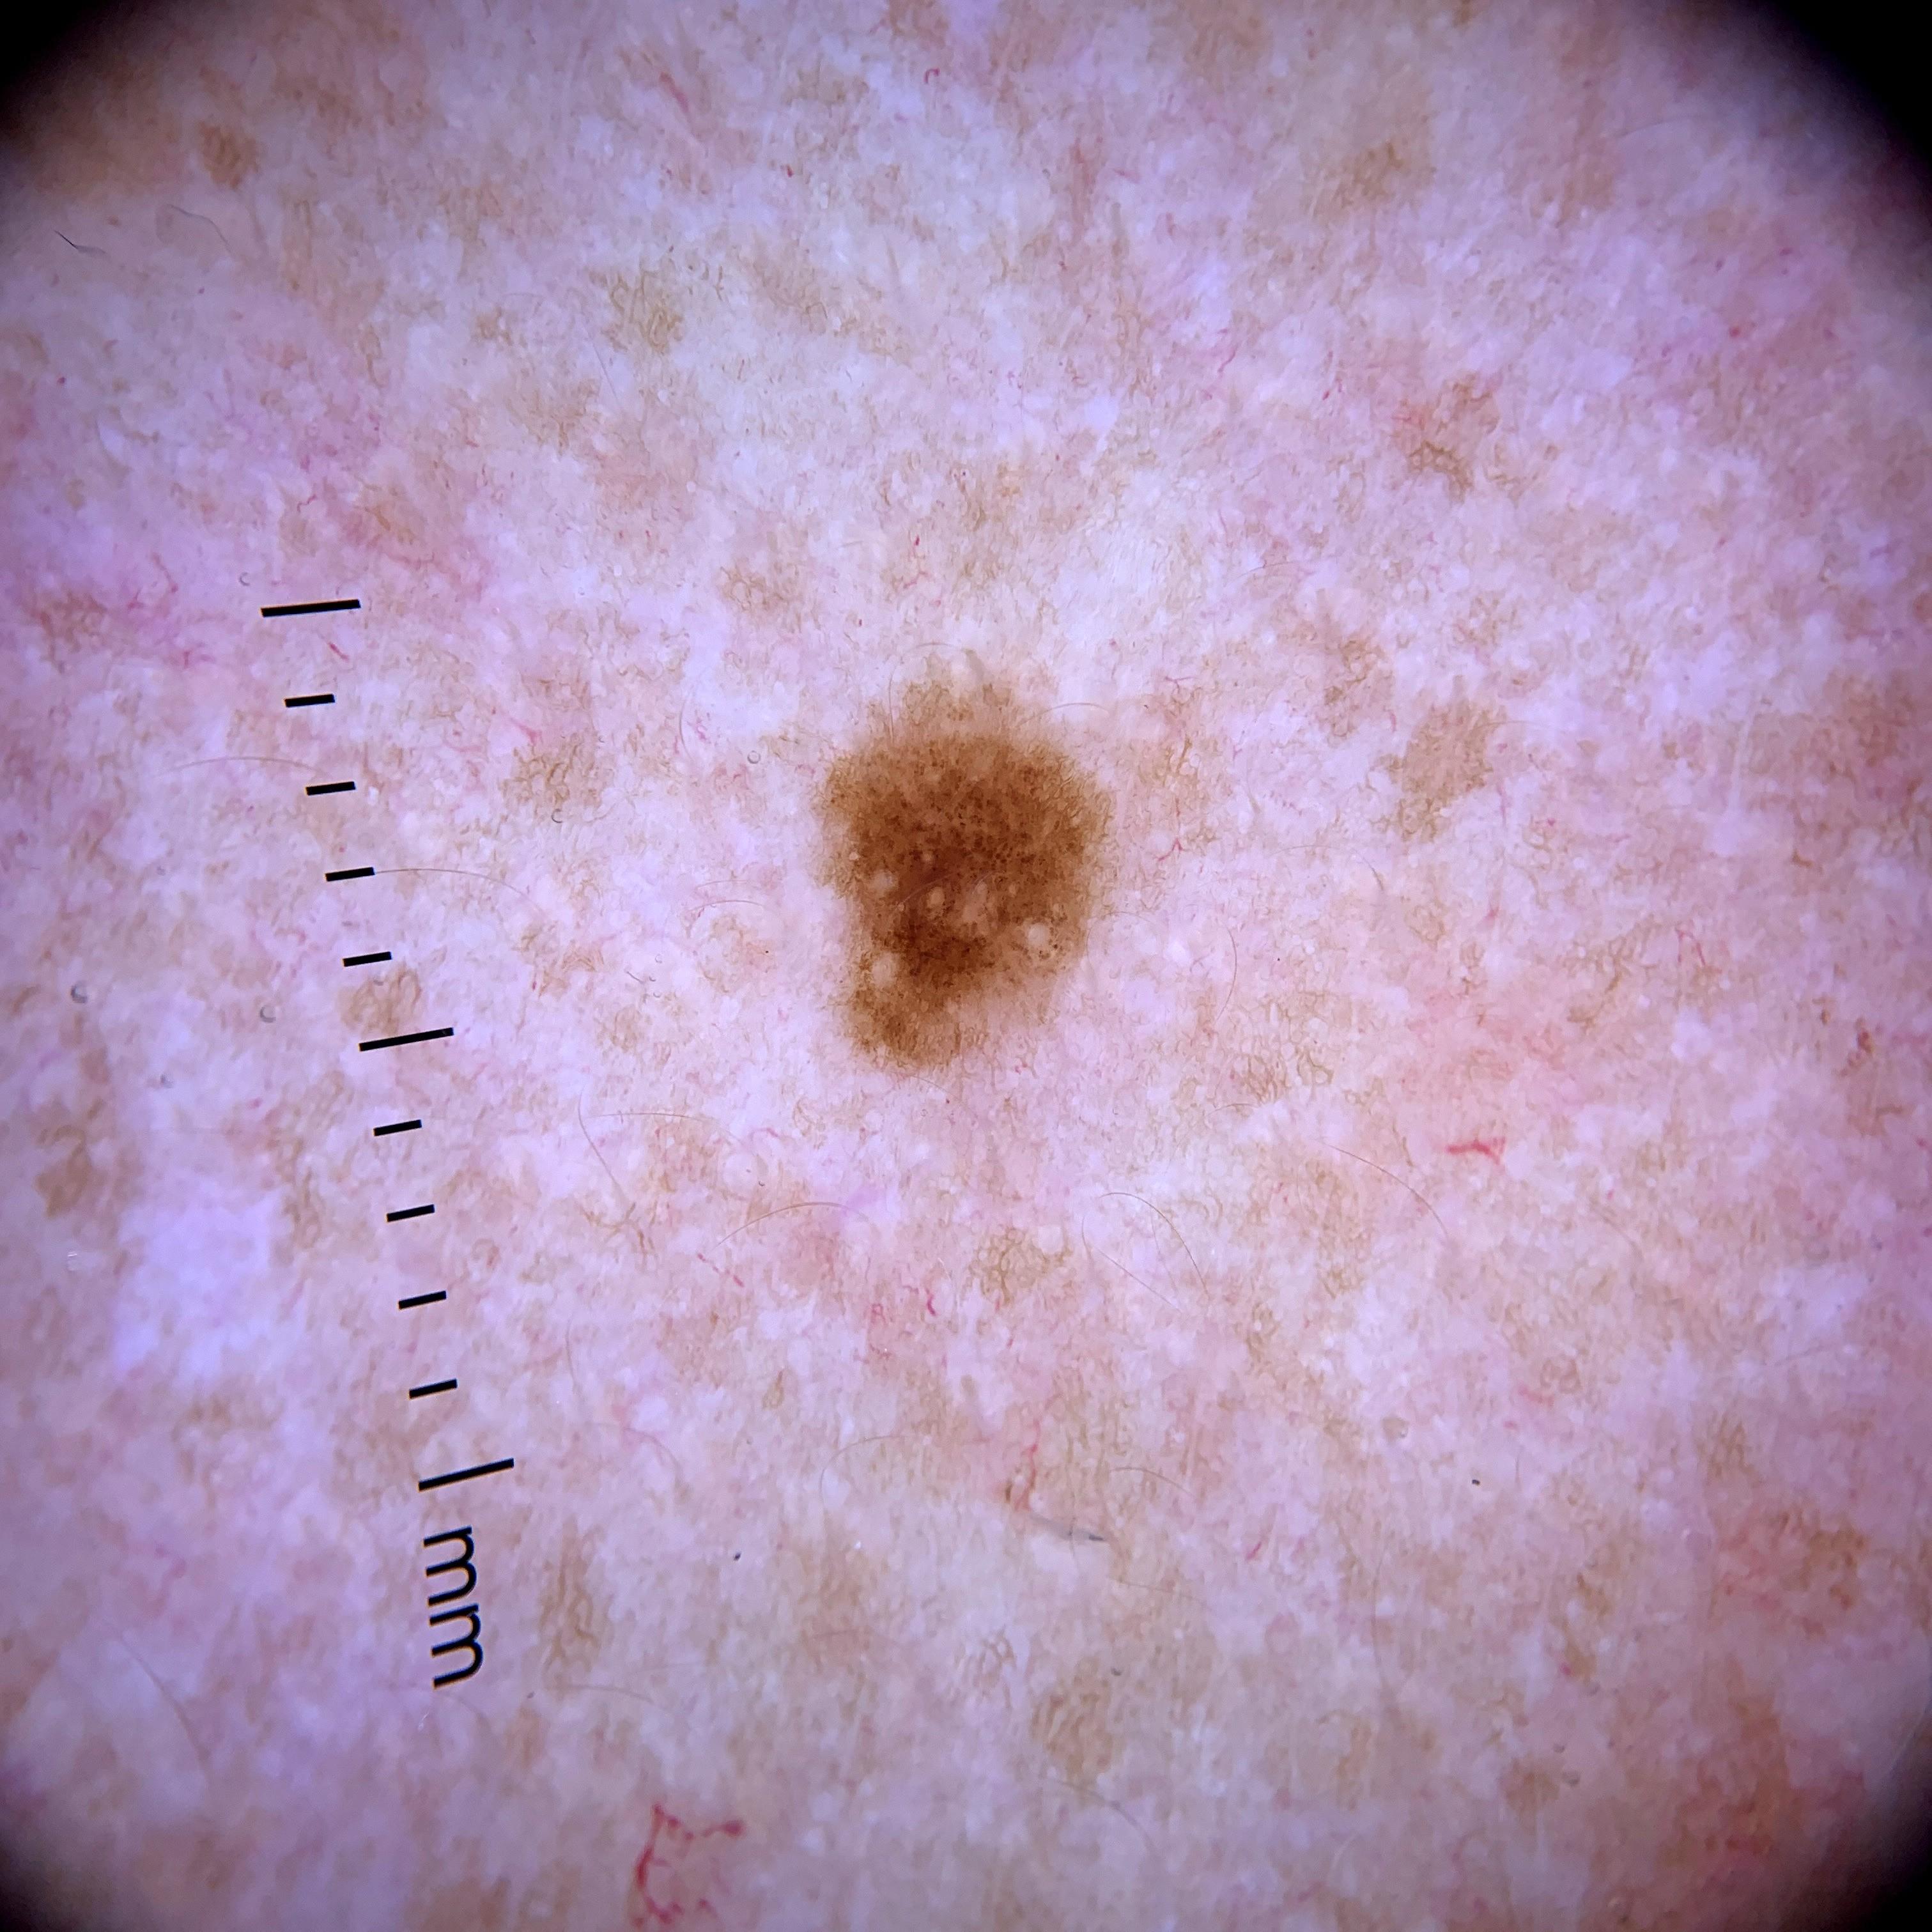

ISIC_0301375

1986 x 1986

Clinical

Field Value

anatom_site_1 Trunk

anatom_site_2 Anterior trunk

anatom_site_general anterior torso

diagnosis_1 Benign

diagnosis_confirm_type single image expert consensus

image_type dermoscopic